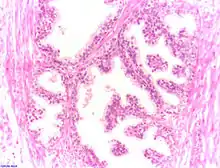

Epiteliul secretor este în mare parte pseudostratificat, fiind format din celule columnare și bazale, ce sunt susținute de o stromă fibroelastică ce conține mici fibre musculare. Epiteliul este foarte variabil, prezentând zone cu celule cuboidale sau cu celule scuamoase, în special în zonele distale și a canalelor[2]. Prezentă în interiorul prostatei, uretra (uretra prostatică) se unește cu cele două canale ejaculatoare.

Sunt două forme clinice: prostatită acută, caracterizată prin edem și infiltrație granulocitară interstițială însoțită de cele mai multe ori de colecții purulente și prostatită cronică, caracterizată prin scleroza țesutului interstițial, atrofie a epiteliului, de cele mai multe ori cu proliferări papilifere.